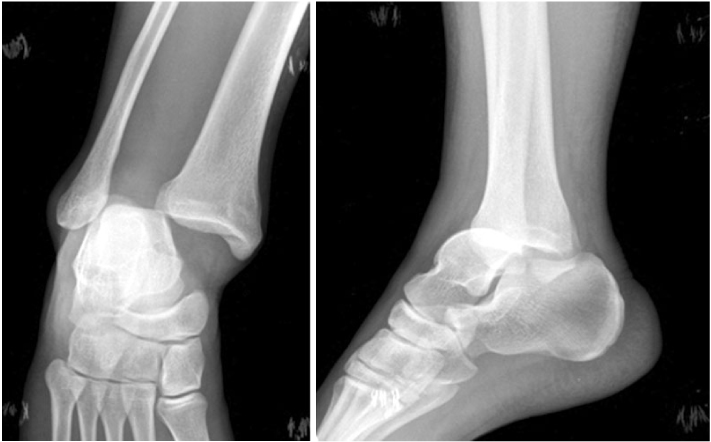

Fig. 2

(A) Anteroposterior view of right ankle shows widening of tibiofibular space and medial clear space.

(B) Lateral view shows equinus and flexion deformity of great toe.

Fig. 2 (A) Anteroposterior view of right ankle shows widening of tibiofibular space and medial clear space. (B) Lateral view shows equinus and flexion deformity of great toe.